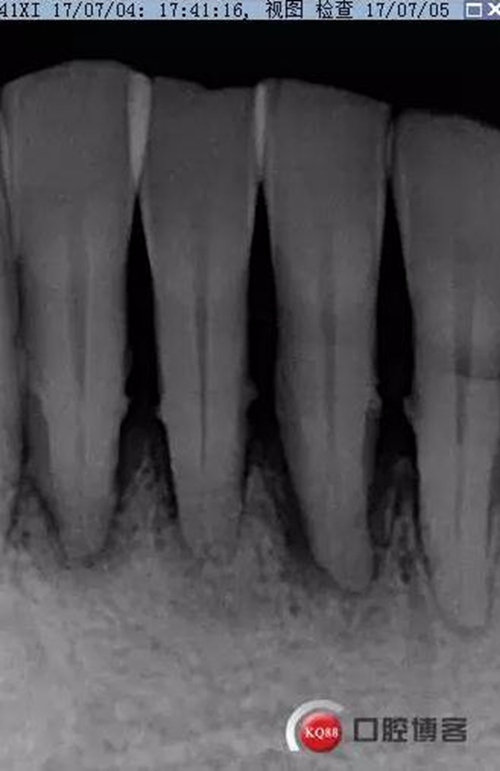

檢查:口腔衛(wèi)生狀況欠佳,牙面可見大量色素附著,牙石II°,尤以下頜前牙舌側(cè)及后牙頰側(cè)為重。牙齦紅腫,BI3-4°,PD下頜前牙區(qū)4-6mm。31松動III°,溫度測試無反應,叩不適。32、41、42松II°+,32溫度測試遲鈍,叩(-)。

X線示牙槽骨吸收,下頜前牙區(qū)可見齦下牙石影像,牙槽骨吸收至根尖1/3,根周透射影像。